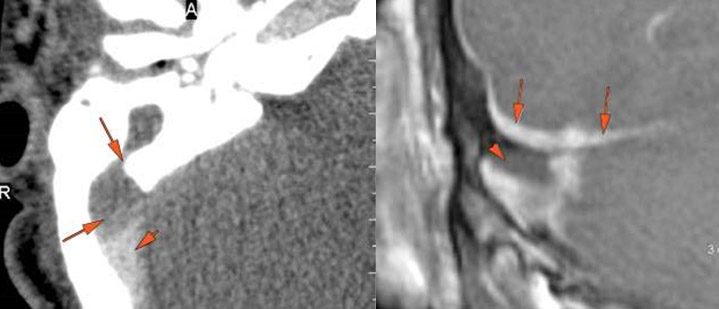

External auditory canal bone is eroded. [Yes/No]

The petrotympanic fissure is eroded. [Yes/No]